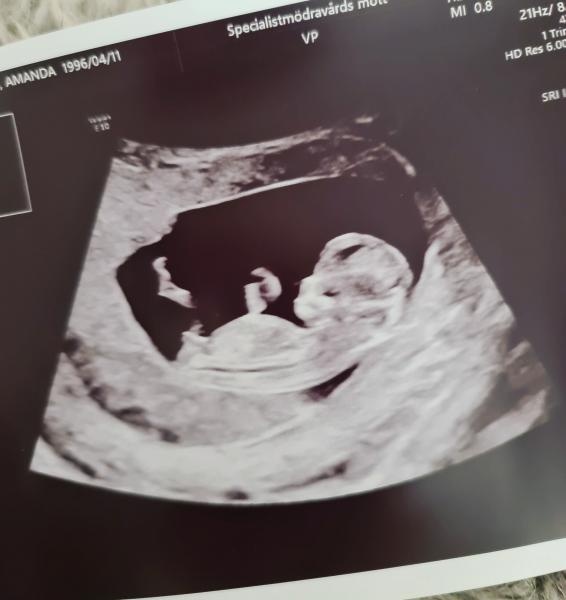

Kub idag, vi båda var nervösa!

Jag var mest nervös att bebisen kanske inte levde (riktigt katastroftänkande, haha)

Jag fick nämligen en stor blödning tidigt i graviditeten där dom inte kunde svara på om det var början på ett missfall, såklart följdes detta upp och lite av blödningen fanns kvar i livmodern 2,5v efter första ul, men då hade embryot växt och hjärtat slog iaf, jag blev ändå väldigt rädd att graviditeten skulle påverkas längre fram. Tänkte att det kanske var ett tecken på att bebisen inte mådde bra!

Ultraljudet idag

gick strålande, där var bebisen! En riktigt vild liten krabat! V11+6 idag och Cub-risk: 1:4693